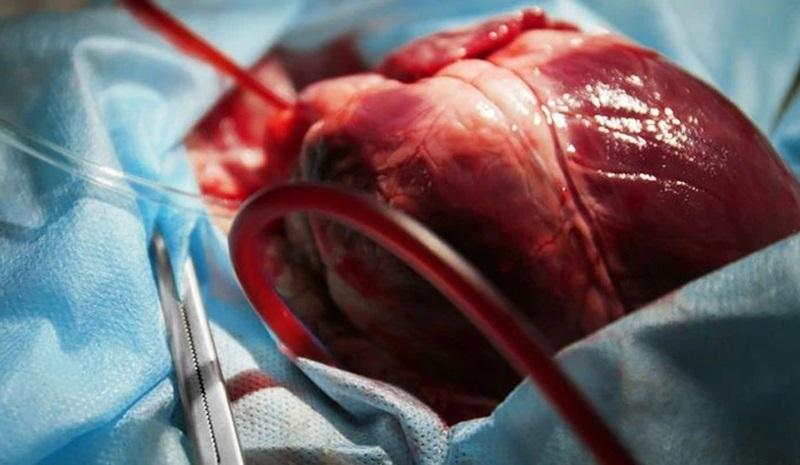

عمل قلب باز یکی از پیچیدهترین و حساسترین جراحیهای پزشکی است که برای درمان بیماریهای قلبی انجام میشود. این عمل که به آن جراحی بایپس عروق کرونر نیز میگویند، میتواند زندگی افرادی را که از مشکلات جدی قلبی رنج میبرند، نجات دهد. در این مقاله، به بررسی دقیق این عمل جراحی، دلایل انجام آن، نحوه انجام، عوارض احتمالی و مراقبتهای پس از عمل میپردازیم.

عمل قلب باز یک جراحی پیچیده است که معمولاً چندین ساعت طول میکشد. مراحل اصلی این عمل به شرح زیر است:

- اتصال به دستگاه قلب و ریه مصنوعی: در اکثر موارد، قلب بیمار موقتاً متوقف میشود و خون از طریق دستگاه قلب و ریه مصنوعی جریان مییابد.

- انجام عمل اصلی: بسته به نوع مشکل، جراح ممکن است رگهای مسدود را بایپس کند، دریچههای معیوب را تعمیر یا تعویض کند، یا سایر اصلاحات لازم را انجام دهد.

- بازگرداندن ضربان قلب: پس از اتمام عمل اصلی، قلب مجدداً به کار انداخته میشود.